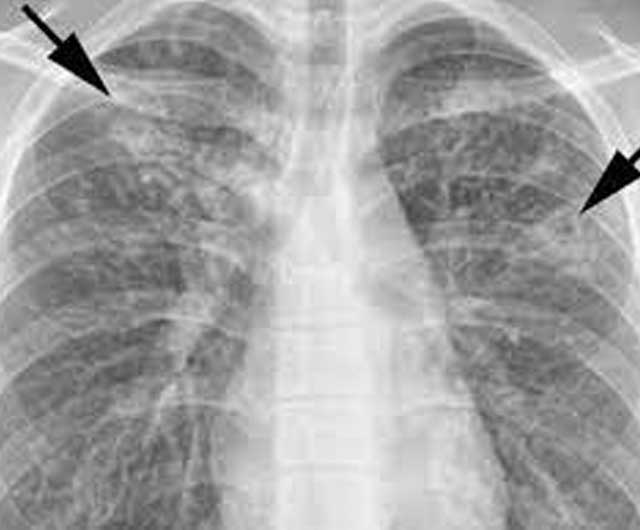

Pulmonary Koch's / Extra-Pulmonary Koch's (TB) and MDR TB

Tuberculosis, MTB, or TB (short for tubercle bacillus) is a common, and in many cases lethal, infectious disease caused by various strains of mycobacteria, usually Mycobacterium tuberculosis. Tuberculosis typically attacks the lungs, but can also affect other parts of the body. It is spread through the air when people who have an active TB infection cough, sneeze, or otherwise transmit respiratory fluids through the air.

Diagnosis of active TB relies on radiology(commonly chest X-rays), as well as microscopic examination and microbiological culture of body fluids. Diagnosis of latent TB relies on the tuberculin skin test (TST) and/or blood tests. Treatment is difficult and requires administration of multiple antibiotics over a long period of time. Social contacts are also screened and treated if necessary. Antibiotic resistance is a growing problem in multiple drug-resistant tuberculosis (MDR-TB) infections. Prevention relies on screening programs and vaccination with the bacillus Calmette–Guérin vaccine